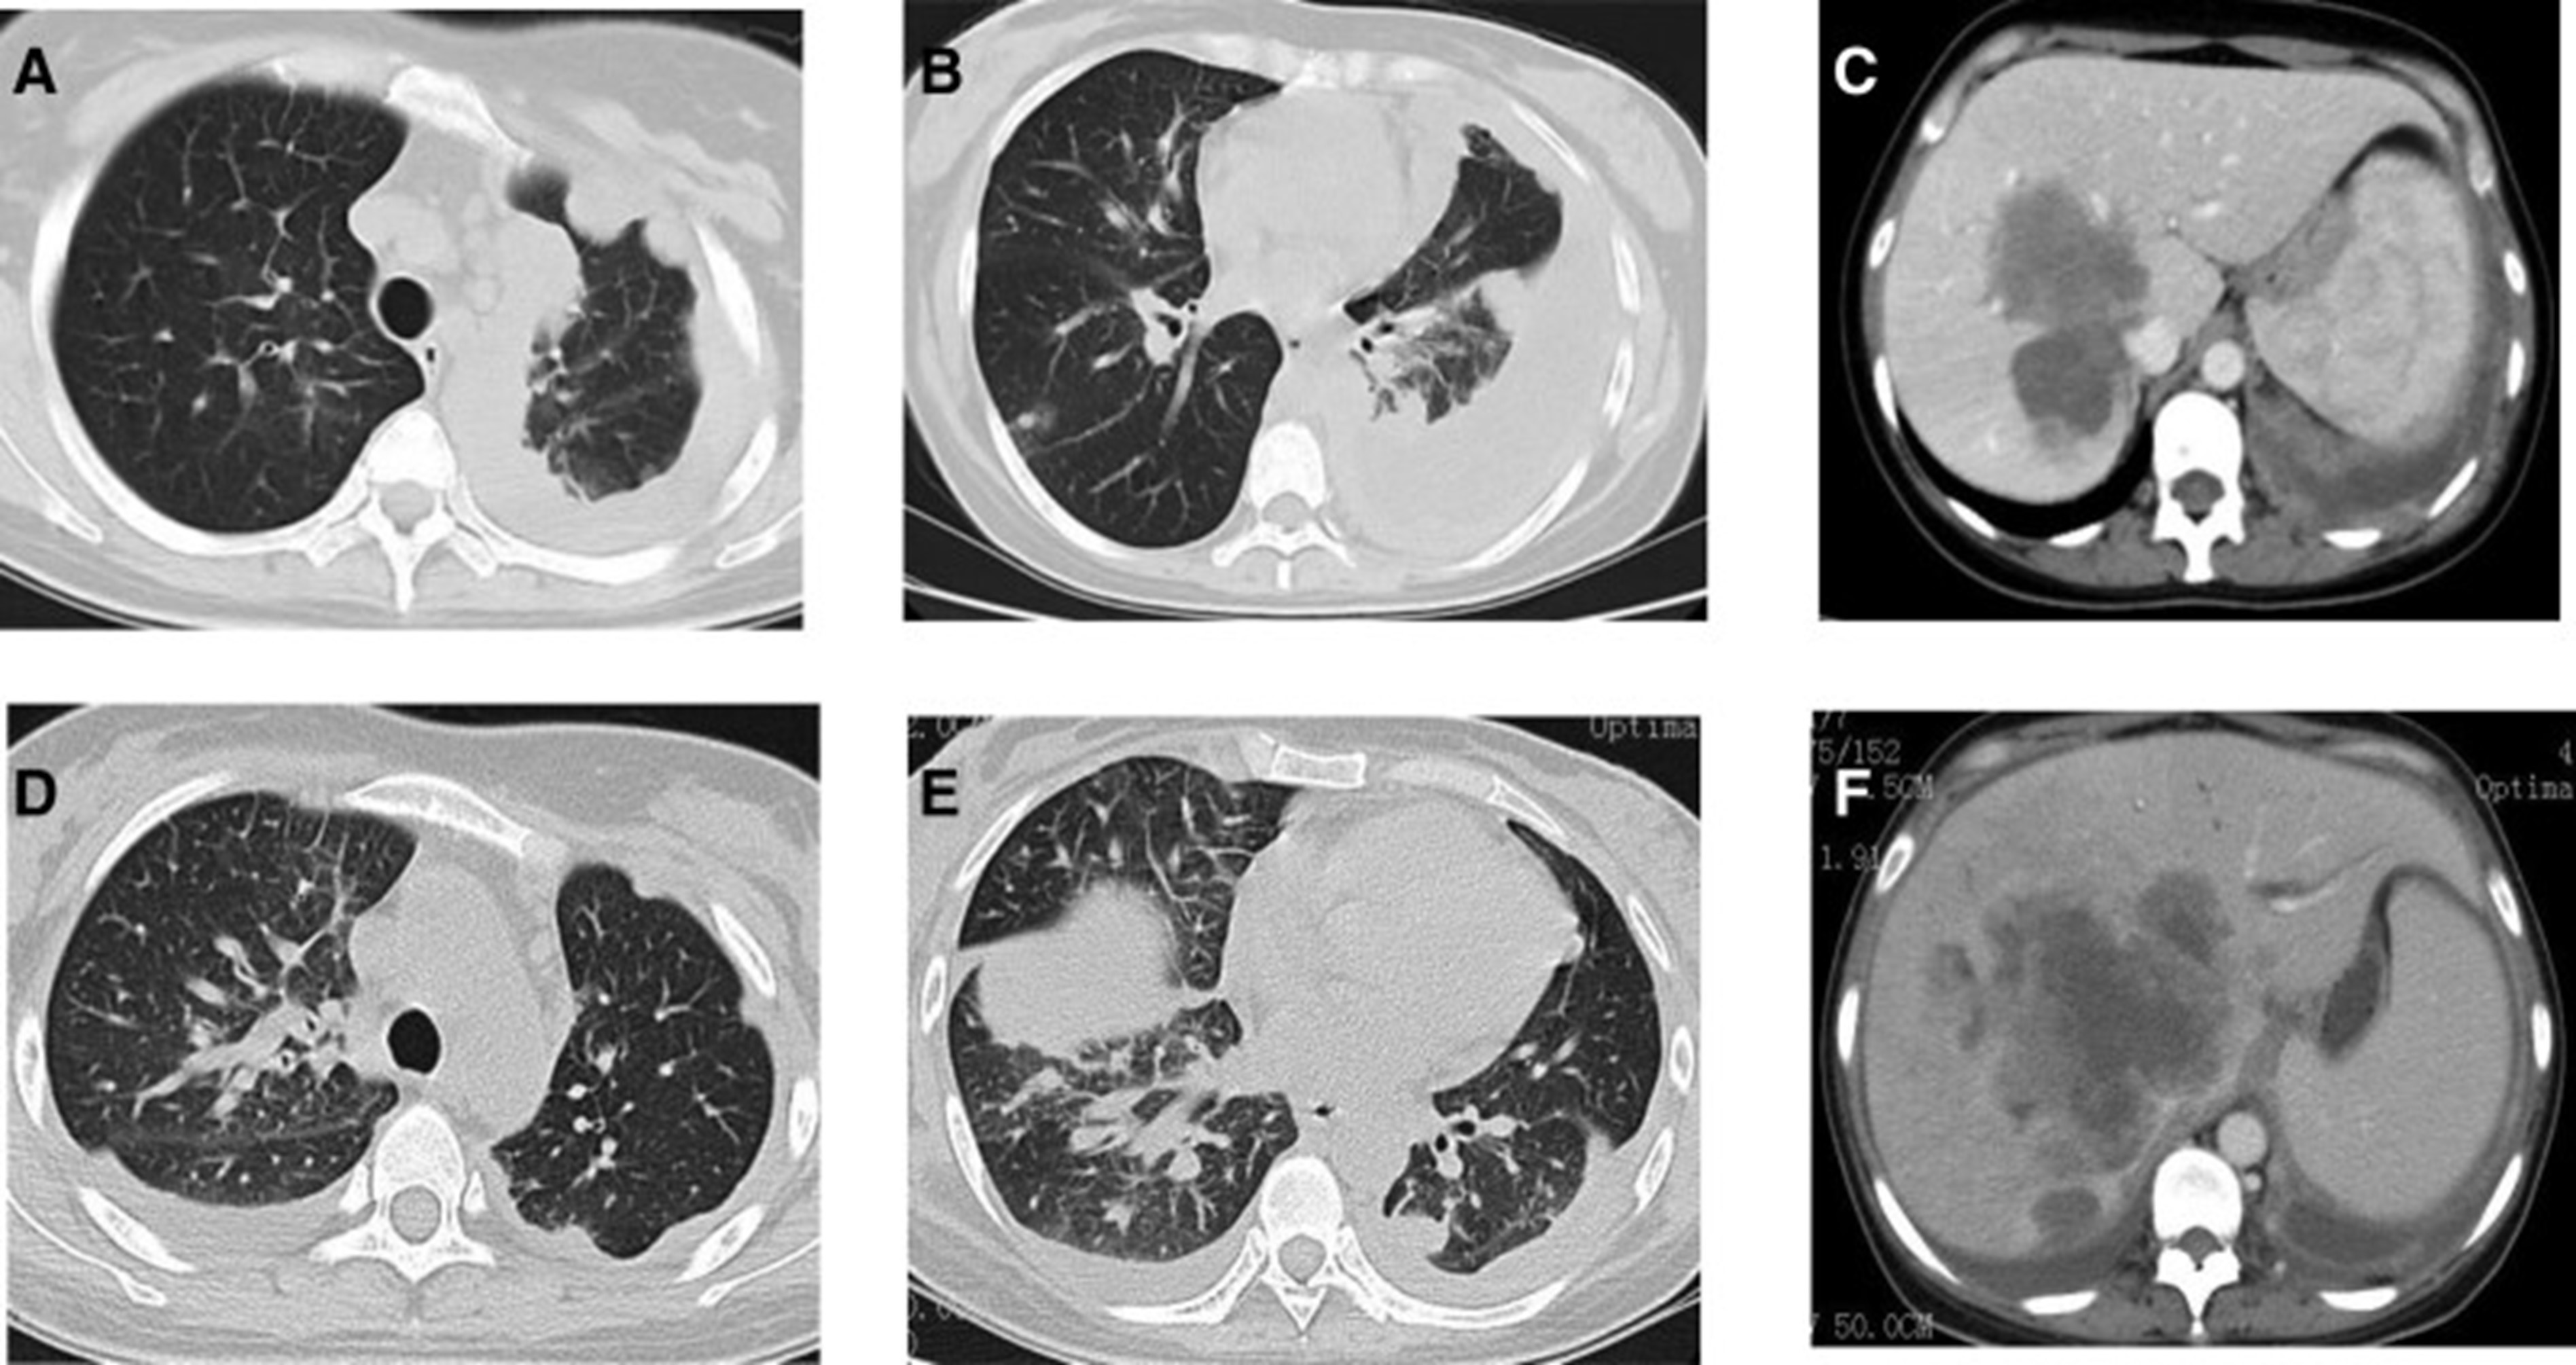

2020年5月1日,患者开始口服艾乐替尼靶向药物进行治疗,2020年6月25日复查,确定治疗效果为PR(部分有效)(根据RECIST1.1)显示肺病灶和肝转移灶明显减少(图1)。(图 3D-F)。2020 年 8 月 27 日复查确定治疗效果为疾病进展(PD, progressive disease),根据 RECIST1.1显示肝脏病变变大(图 1)(图 4A-D)。进行了第二次肝活检,随后的病理学显示“(肝)低分化癌,结合免疫组织化学分析考虑肺腺癌转移”。组织活检进行了第二轮基因检测,结果显示“BRAFV600E 14.79%,EML 4-ALK fusion 14.47%”(图 1)(图 5)。2020年9月20日,对患者我以为用恩沙替尼联合达拉非尼靶向治疗。治疗开始后,患者出现明显发热、寒战、乏力和厌食。期间患者左侧出现大量胸腔积液,胸腔积液中脱落细胞为“非典型细胞,考虑为腺癌”。随后,该患者接受了 1 次胸腔内铂输注。

和 2020 年 8 月.jpg)

图 5:2020 年 6 月(A 和 B)和 2020 年 8 月(C 和 D)的 CT 扫描。CT = 计算机断层扫描。

1个月后复查显示肺部和肝内病变进展(图1)。(图 6A-C)(根据RECIST1.1),她的抗肿瘤治疗改为“培姆曲塞加卡铂和贝伐单抗”的治疗一个周期。2020年12月至2021年1月,再次改变患者的治疗方案,这次改为“劳拉替尼联合达拉非尼”靶向治疗。使用 PD 联合胸部和腹部 CT 评估疗效(图 1)。(图 6D-F)(根据 RECIST1.1)。患者无法耐受化疗、靶向治疗、IO 治疗或任何其他积极的抗肿瘤治疗。这是因为患者的一般情况较差,包括发烧、腹痛和胆红素水平升高等症状。随后,给予患者静脉营养、镇痛等对症支持治疗。患者于 2021 年 2 月 4 日去世,总生存期(OS)为 10 个月。

和 2022 年 1 月 (D-F) 的 CT 扫描.jpg)

图 6:2020 年 11 月 (A-C) 和 2022 年 1 月 (D-F) 的 CT 扫描。CT = 计算机断层扫描。